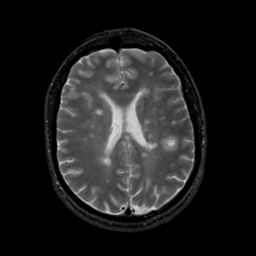

MR Study #17, July 7, 1991 -- Slice #31

[Home][Help][Clinical][Tour 1][Tour 2] Slice 31